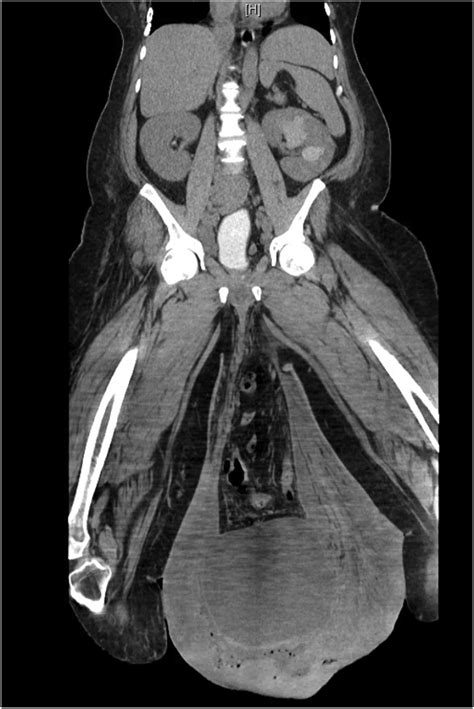

Elephantitis Of The Testicals

Elephantitis of the testicals, also known as elephantiasis of the scrotum, is a rare and severe condition characterized by the enlargement of the scrotum due to lymphatic obstruction. This condition is typically caused by filariasis, a parasitic infection transmitted by mosquitoes. Understanding the causes, symptoms, diagnosis, and treatment options for elephantitis of the testicals is crucial for effective management and prevention.

• Scrotal Swelling: The most noticeable symptom is the enlargement of the scrotum, which can become massive in severe cases.

• Skin Changes: The skin of the scrotum may become thickened, hardened, and discolored.

• Mobility Issues: The enlarged scrotum can interfere with mobility and daily activities.

• Ultrasound: Ultrasound imaging can help visualize the lymphatic vessels and assess the extent of obstruction.